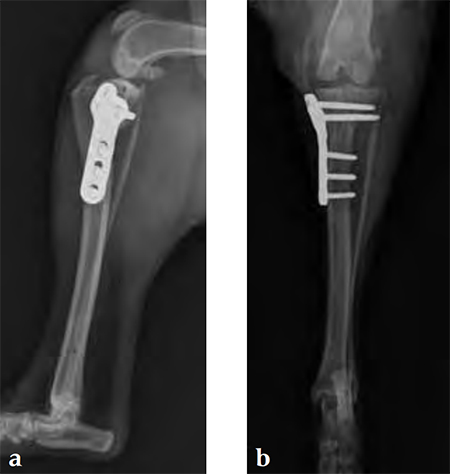

Case 2: Australian cattle dog

(Case provided by Brian Beale, Houston, USA)

An 8-year-old, female, spayed, 24 kg Australian cattle dog. This breed has short stocky legs and is very energetic and strong. The added strength of the 3.5 mm plate over the TPLO 2.7 mm plate was an advantage. The smaller head profile and shorter length of the TPLO 3.5 mm small stature plate allowed it to fit nicely on this patient.